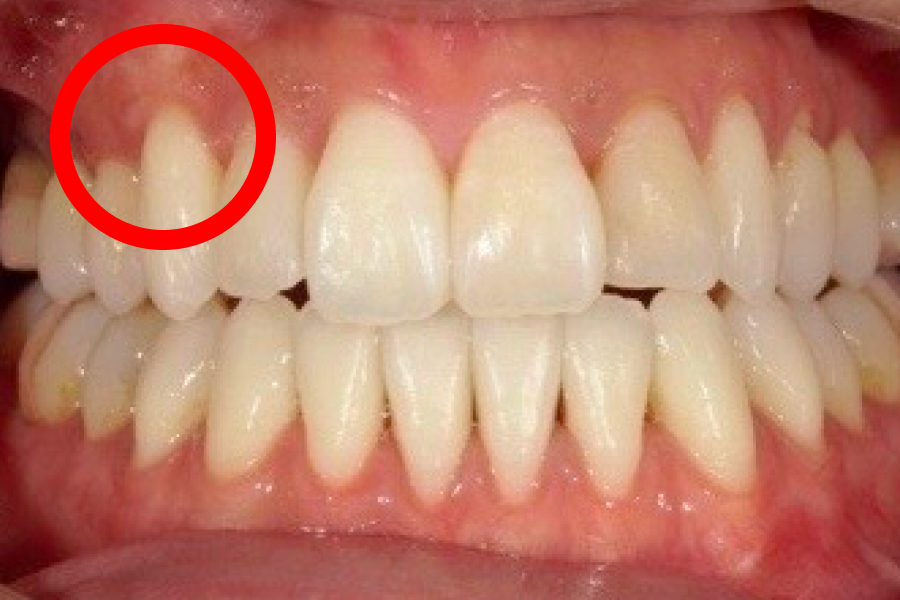

歯肉退縮が進むと、まず歯ぐきが下がって本来覆われていた根元が見えるため歯が長く見えるようになり、ついで歯根が露出することで冷水やブラッシングでしみる知覚過敏や根元のむし歯(歯根う蝕)、歯間が広がって食片が挟まりやすい・黒三角が目立つといった審美面の問題が生じます。

歯茎下がり症例

施術前

施術後